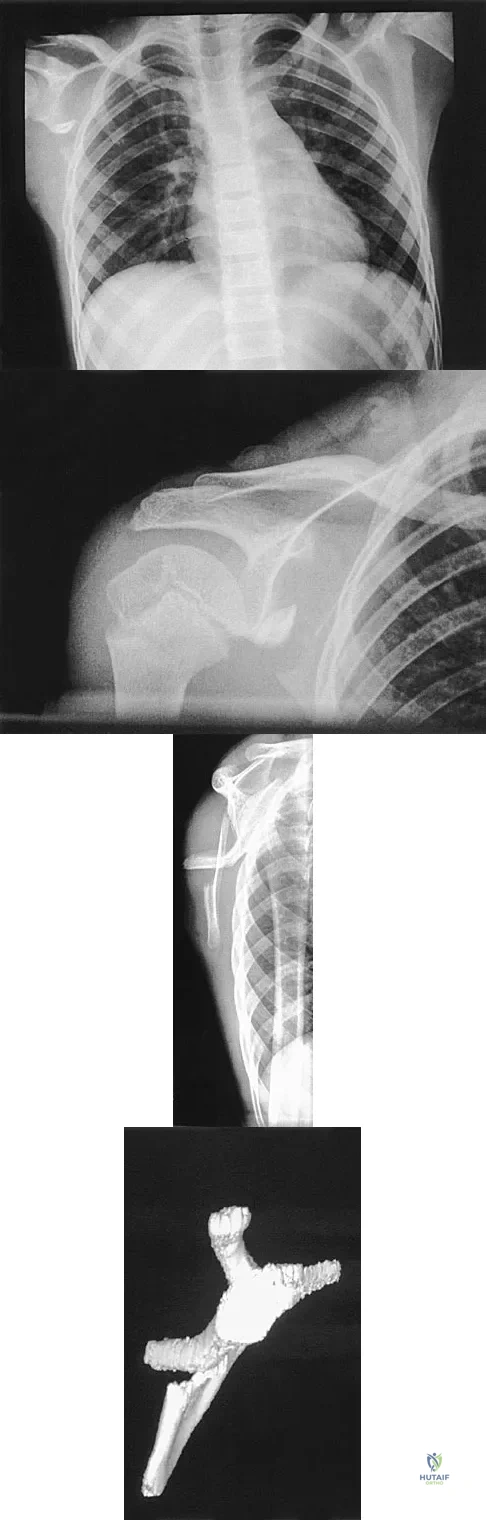

Question 24

A 12-year-old boy has severe left shoulder pain after being struck by an automobile. A chest radiograph, AP and lateral radiographs, and a CT scan with three-dimensional reconstruction of the scapula are shown in Figures 38a through 38d. Management should consist of

Explanation